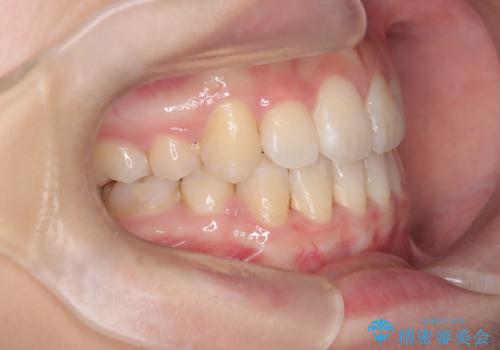

【埋伏歯】犬歯の牽引を行った矯正歯科治療

- 八重歯を主訴に来院されました。

左側犬歯が埋伏していましたが、第一小臼歯(4番目の歯)を抜歯したことでできたスペースに牽引し、右側の飛び出した八重歯を含め、歯全体を整列することができ患者様も満足していただきました。